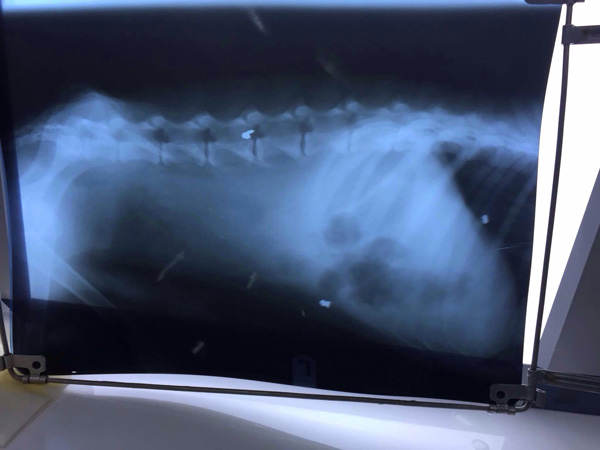

«Մեզ ահազանգողները նշել էին, որ շունը, հավանաբար, մեքենայի տակ է ընկել, սակայն նրան կլինիկա բերելուց ու ռենտգեն անելուց հետո պարզվեց, որ կենդանուն կրակել են ու պարկուճը դիպել է հենց ողնաշարին, ինչի հետևանքով էլ նա հենաշարժողական լուրջ խնդիրներ ունի ու այլևս չի կարողանա ինքնուրույն քայլել», – պատմեց «Փոուզիթիվի» համահիմնադիրներից Աննան:

Վերադառնալով հրազենի կրակոցից խեղված, վերևում նշված շան դեպքին: Այս պահին կենդանին չափազանց հյուծված է ու նրա բուժման, հնարավորինս վերականգնման համար «Փոուզիթիվի» կամավորներն աջակցության կարիք ունեն: